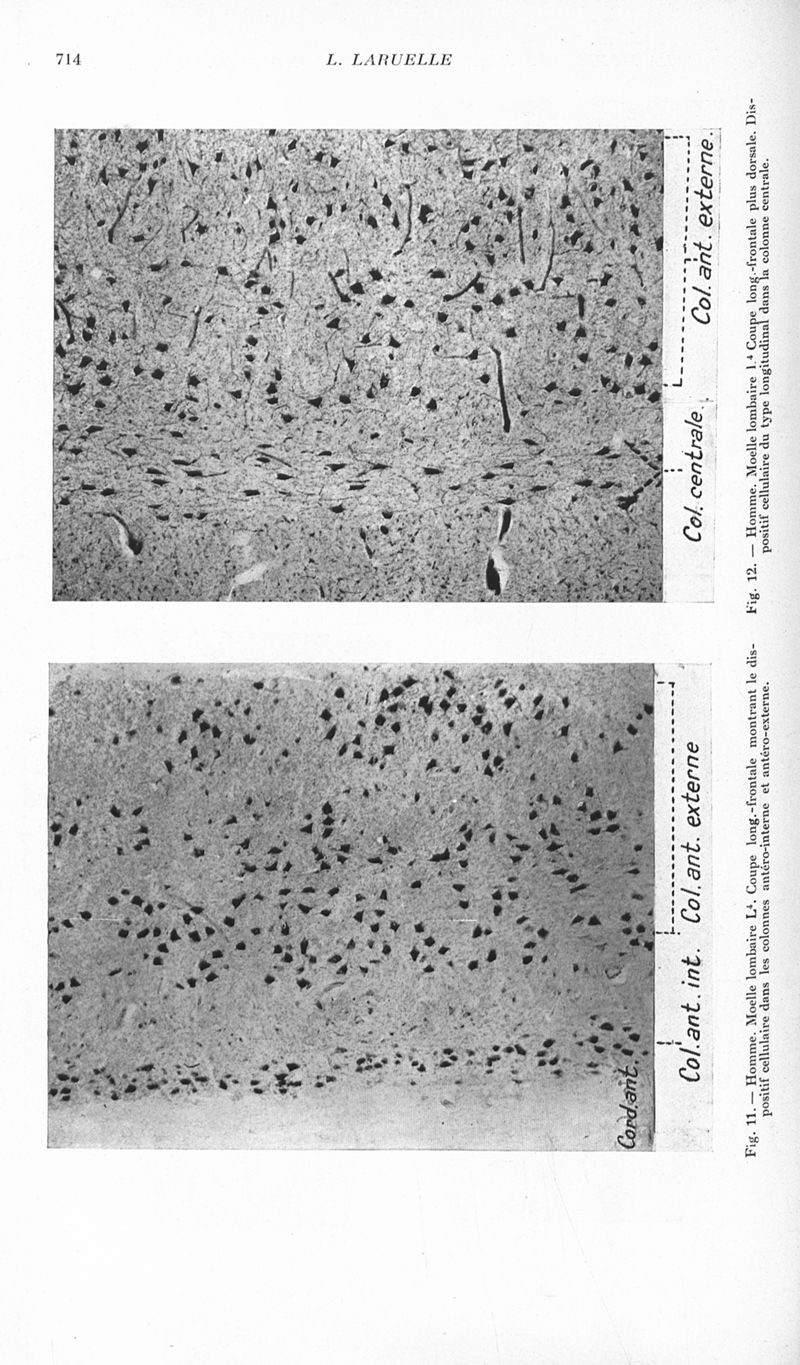

Revue neurologique

1937, vol 1. - Paris : Masson , 1937.